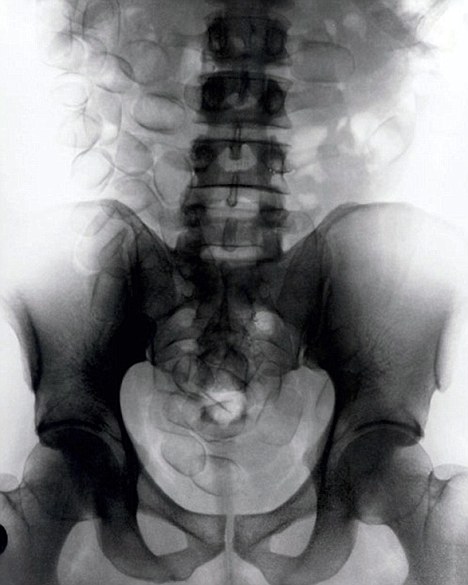

現(xiàn)年30歲的菲達(dá)利斯(Fidelis Ozouli)冒著生命危險(xiǎn)將重達(dá)1公斤的毒品吞下,被抓后卻辯稱不知道吞下的是毒品。當(dāng)時(shí),曼徹斯特機(jī)場的海關(guān)人員看到毒販菲達(dá)利斯臃腫的肚腩,顯得很不自然,于是開始懷疑。檢查人員用X射線機(jī)照他的胃部時(shí),發(fā)現(xiàn)了大量可卡因。目前他已被送往附近醫(yī)院,以確保排出所有的毒品。